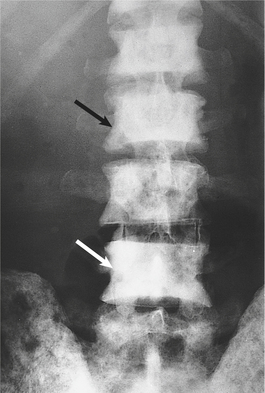

Vascular invasion by the tumour results in blood-borne metastases, most commonly to bone, lungs and liver. The most frequent sites of bone metastases are the pelvis, lumbosacral spine and proximal femur, less frequently the ribs and skull. Tumour emboli may reach the vertebrae by venous spread to the lung, then by passing through the pulmonary capillaries to enter the arterial circulation. An alternative mechanism is by retrograde venous spread through the vertebral venous plexus, because the blood flow in these veins may reverse due to physiological variation in the intra-abdominal pressure.

Bone metastases are usually osteosclerotic, with proliferation of osteoblasts and areas of new bone formation occurring in association with the neoplastic cells (Fig. 20.12). The osteoblast proliferation results in a raised serum alkaline phosphatase level.

image

Fig. 20.12 Metastases from carcinoma of the prostate. X-ray of lumbar spine, including part of iliac bones, showing numerous sclerotic (white) metastases (arrowed).